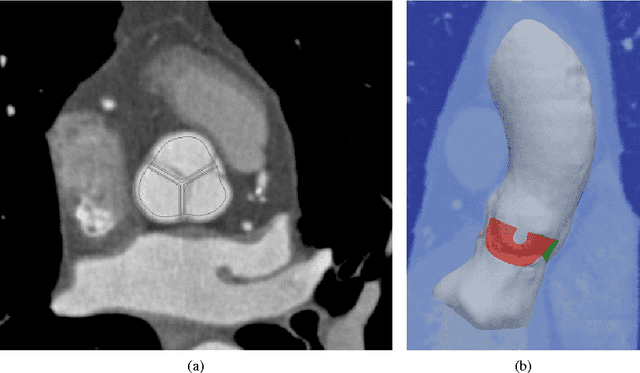

Abstract:Each year, approximately 300,000 heart valve repair or replacement procedures are performed worldwide, including approximately 70,000 aortic valve replacement surgeries in the United States alone. This paper describes progress in constructing anatomically and physiologically realistic immersed boundary (IB) models of the dynamics of the aortic root and ascending aorta. This work builds on earlier IB models of fluid-structure interaction (FSI) in the aortic root, which previously achieved realistic hemodynamics over multiple cardiac cycles, but which also were limited to simplified aortic geometries and idealized descriptions of the biomechanics of the aortic valve cusps. By contrast, the model described herein uses an anatomical geometry reconstructed from patient-specific computed tomography angiography (CTA) data, and employs a description of the elasticity of the aortic valve leaflets based on a fiber-reinforced constitutive model fit to experimental tensile test data. Numerical tests show that the model is able to resolve the leaflet biomechanics in diastole and early systole at practical grid spacings. The model is also used to examine differences in the mechanics and fluid dynamics yielded by fresh valve leaflets and glutaraldehyde-fixed leaflets similar to those used in bioprosthetic heart valves. Although there are large differences in the leaflet deformations during diastole, the differences in the open configurations of the valve models are relatively small, and nearly identical hemodynamics are obtained in all cases considered.